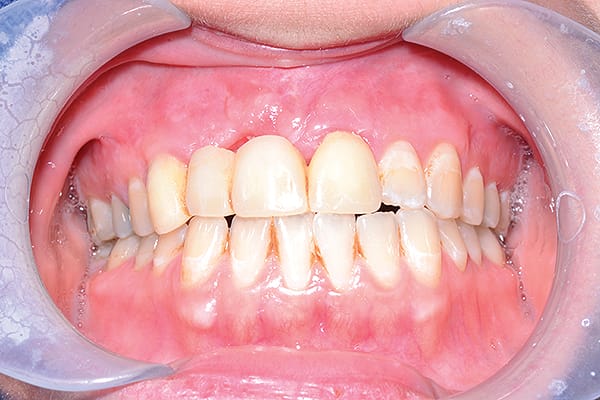

Figure 20

Figure 20 Full view at 1.5-year follow-up. (Fig 20 courtesy of Dr. Heggerick and Mr. Momma)